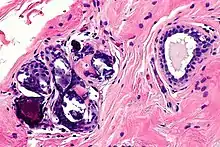

In most cases, calcification and cysts are the biggest threat of breast augmentation surgery. Fat stem cells failed to pick up a new blood supply will die and be removed from the body by immune cells. However, when this clearing process miss removing dead cells the cluster will lead to calcification and cysts formation. These are visible on the breast as lump sometimes and are more dangerous when these un-picked up dead cells are detected as cancer cells which disturbs accurate diagnosis of breast cancer. The calcified tissue will be diagnosed as a 'benign' cancer and not cause any harm. However, if the tissue is severely damaged the entire breast needs to be removed. Once a patient is diagnosed with calcification of breast implant, regular mammograms should be done to monitor the possible cancer development.[16]